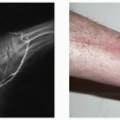

The most widely accepted pressure sore staging system was revised by the National Pressure Ulcer Advisory Panel in 2007 to include the original four stages and an additional two stages regarding deep tissue injury and unstageable pressure sores (Table 98.1). Stage I includes intact skin with nonblanching erythema, stage II includes partial-thickness loss of dermis, stage III includes full-thickness tissue loss, and stage IV includes exposed bone, tendon, or muscle.1 Additional classification includes suspected deep tissue injury, usually characterized by maroon localized intact skin or blood-filled blister, and unstageable, which is a full-thickness ulcer with eschar at the base. Limitations exist in this system; signs like skin erythema can be present in more than one stage and dark skin pigmentation can actually obscure the presence of erythema, necessitating other diagnostic signs like increased skin temperature, edema, and induration, to accurately stage the wound. Long-standing wounds of the pelvic girdle warrant careful examination and possible imaging to evaluate for extension into deeper structures, such as the acetabulofemoral joint.

Compression of soft tissues results in ischemia and, if not relieved, it will progress to necrosis and ulceration, even in well-vascularized areas (Figure 98.3). What is seen on the surface is often merely the tip of the iceberg, as confirmed by pressure measurements taken over bony prominences8 (Figure 98.4). In susceptible patients, progression from excessive pressure to irreversible ischemia and tissue necrosis is accelerated by infection, inflammation, edema, and other factors that are not yet understood.